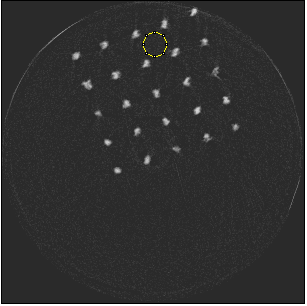

Figure 5 illustrates a single slice spectral reconstruction of the Ti scaffold. Varying levels of streak artefacts can be seen across the spectral reconstructions. The spectral reconstructions for the energy ranges 35 to 80 keV, 55 to 80 keV, and 62 to 80 keV shown in figure 5, exhibit reduced streak artefacts. A region-of-interest (ROI) analysis was performed in the immediate vicinity of the metal region where the streaks are more pronounced. Average attenuation coefficent of air close to zero conveys less regional noise/artefacts. The regional average attenuation coefficient () of the non-metal (air) region in 55 to 80 keV reconstruction (figure 5c) shows reduced artefacts. Even though minor streaks and statistical noise appear in figure 5d due to photon limitation, the artefacts are less pronounced in comparison to the wide energy acquisition in figure 5a.